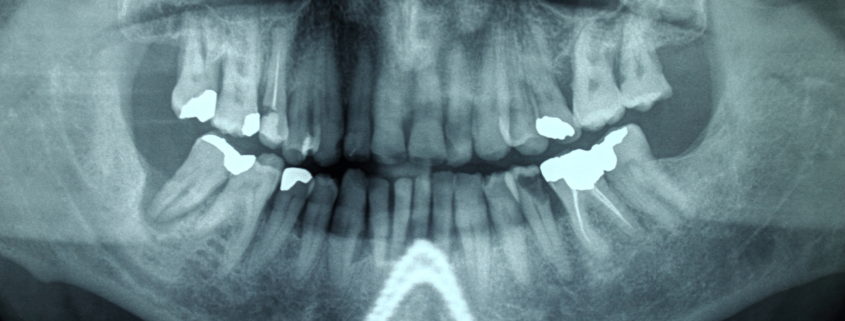

Cos’è l’Ortopantomografia?

Con il termine ortopantomografia si intende quell’esame radiografico che ci permette di vedere entrambe le arcate dentarie in una sola radiografia.